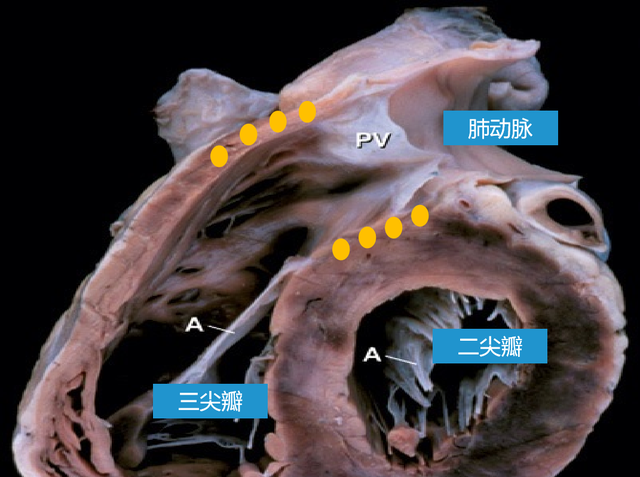

(二)右心室 肺动脉口 动脉圆锥 膜部室间隔 室上嵴 前瓣 三尖瓣 隔瓣

循环系统 脉管系统课件 (四)左心室 右心室左后方,室腔近似圆锥形